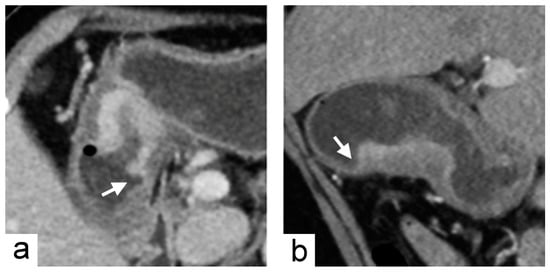

Figure 3. Chromosomal instability subtype gastric cancer in a 79-year-old female who underwent preoperative contrast-enhanced computed tomography. (a) portal venous phase axial and (b) arterial phase sagittal images showed focal wall thickening of the greater curvature side of the stomach with the largest diameter of 3.1 cm. In the imaging traits evaluation, the tumor morphology was defined to be acute tumor transition angle (arrows in (a,b)), well-defined margin and polypoid shape.